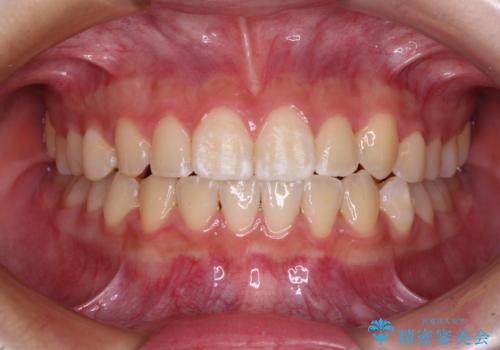

30代女性 前歯のがたつき